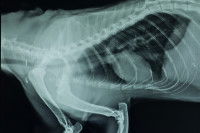

Le squelette du chat comprend en moyenne 230 à 250 os. C'est nettement moins que le nombre d'os du chien, qui en comprend entre 280 et 300. C'est tout de même bien plus que l'être humain, qui n'en compte que 206.

Comme les autres mammifères, le chat est doté d'une colonne vertébrale, qui relie la base de son crâne à sa queue. Elle abrite et protège la moelle épinière, qui correspond au réseau de nerfs chargé de transmettre les messages depuis le cerveau vers le reste du corps, et inversement. Les omoplates, les côtes, les hanches y sont rattachées.

Comme son nom l'indique, la colonne vertébrale est constituée de vertèbres, que l'on peut ranger en plusieurs catégories en fonction de leur localisation :

Cela fait environ 50 vertèbres dans le cas général, et 30 lorsque le petit félin n'a pas de queue.

Quoi qu'il en soit, la colonne vertébrale possède la particularité d'être très souple : c'est ce qui lui permet d'être aussi agile. Grâce à cela, il peut par exemple s'étirer massivement, ou même se retourner sur lui-même.

Comme l'humain et le chien, le chat est doté de côtes. Il s'agit d'os plats situés dans le thorax et protégeant divers organes vitaux : le coeur, les poumons, l'estomac...

Le chat possède 13 paires de côtes, qui sont rattachées à leur base à la colonne vertébrale. C'est donc autant que le chien, et une de plus que l'être humain, qui ne possède que 12 paires.